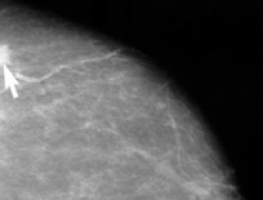

With mice bearing human cancer cells that are targeted by trastuzumab, they showed that for PET imaging the zirconium-labelled antibody worked as well as those produced via established methods.